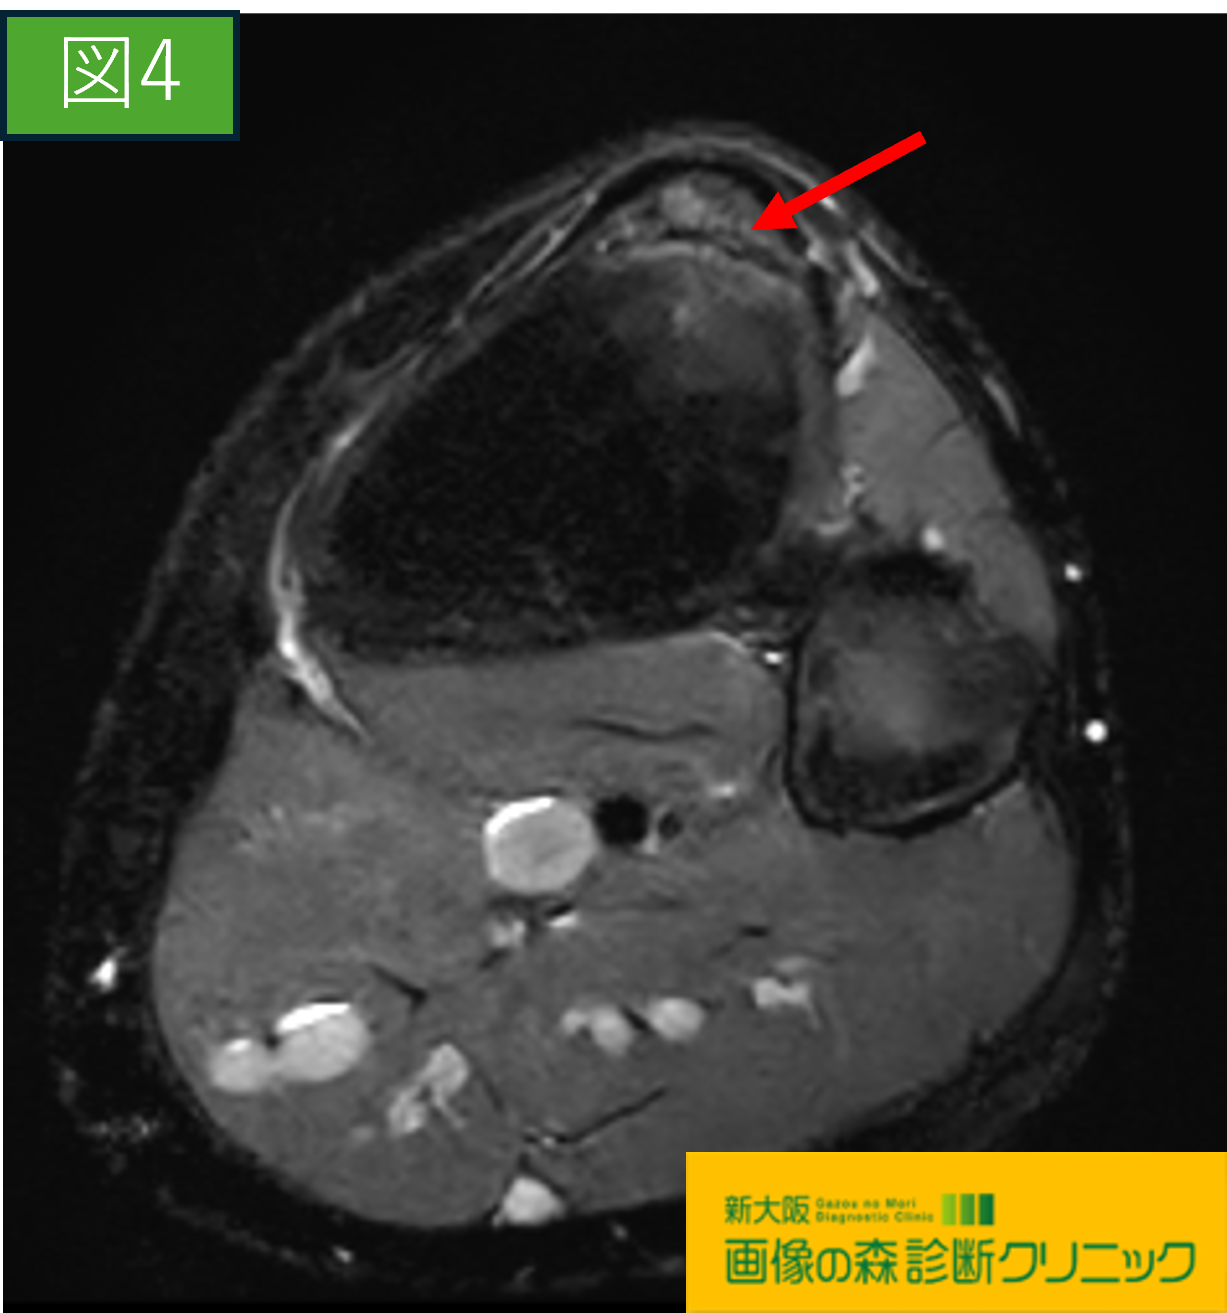

画像から図1・図3は正常膝関節の画像です。

図2・図4ではOsgood-Schlatter病の症例を示しています。

〇続けて図3・図4の画像は膝関節を輪切りで観察しています。

図3は正常画像

図4の赤矢印には、脛骨粗面(膝蓋骨のすぐ下)に

横方向に明瞭な亀裂が認められます。